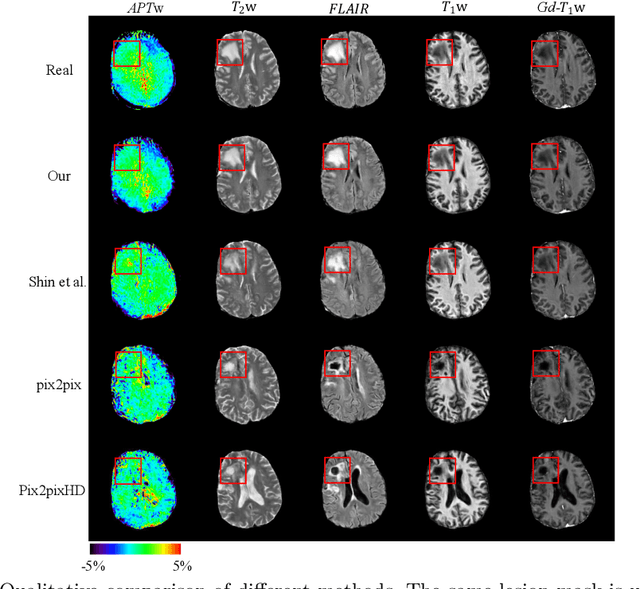

Abstract:Data-driven automatic approaches have demonstrated their great potential in resolving various clinical diagnostic dilemmas in neuro-oncology, especially with the help of standard anatomic and advanced molecular MR images. However, data quantity and quality remain a key determinant of, and a significant limit on, the potential of such applications. In our previous work, we explored synthesis of anatomic and molecular MR image network (SAMR) in patients with post-treatment malignant glioms. Now, we extend it and propose Confidence Guided SAMR (CG-SAMR) that synthesizes data from lesion information to multi-modal anatomic sequences, including T1-weighted (T1w), gadolinium enhanced T1w (Gd-T1w), T2-weighted (T2w), and fluid-attenuated inversion recovery (FLAIR), and the molecular amide proton transfer-weighted (APTw) sequence. We introduce a module which guides the synthesis based on confidence measure about the intermediate results. Furthermore, we extend the proposed architecture for unsupervised synthesis so that unpaired data can be used for training the network. Extensive experiments on real clinical data demonstrate that the proposed model can perform better than the state-of-theart synthesis methods.

Abstract:Data-driven automatic approaches have demonstrated their great potential in resolving various clinical diagnostic dilemmas for patients with malignant gliomas in neuro-oncology with the help of conventional and advanced molecular MR images. However, the lack of sufficient annotated MRI data has vastly impeded the development of such automatic methods. Conventional data augmentation approaches, including flipping, scaling, rotation, and distortion are not capable of generating data with diverse image content. In this paper, we propose a generative adversarial network (GAN), which can simultaneously synthesize data from arbitrary manipulated lesion information on multiple anatomic and molecular MRI sequences, including T1-weighted (T1w), gadolinium enhanced T1w (Gd-T1w), T2-weighted (T2w), fluid-attenuated inversion recovery (FLAIR), and amide proton transfer-weighted (APTw). The proposed framework consists of a stretch-out up-sampling module, a brain atlas encoder, a segmentation consistency module, and multi-scale labelwise discriminators. Extensive experiments on real clinical data demonstrate that the proposed model can perform significantly better than the state-of-the-art synthesis methods.